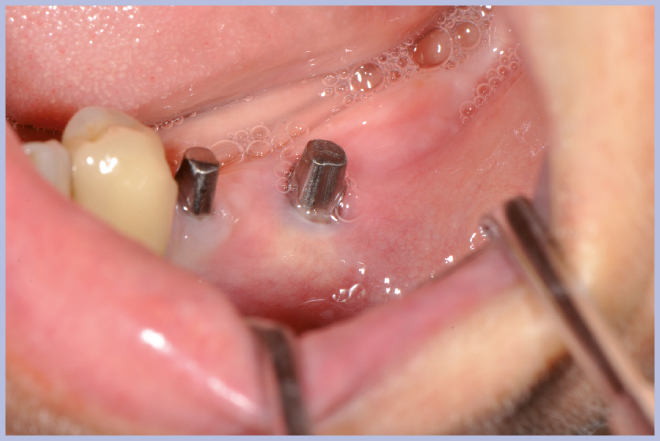

Viene quindi richiesto al tecnico di modificare in laboratorio la mascherina radiologica mediante il posizionamento delle boccole di guida adatte agli impianti da posizionare (Exacone® 6.5 e Exacone® 3,3×8) in asse con gli analoghi del modello Master 3D ed eliminando il repere radiologico standardizzato, trasformandola così nella dima chirurgica (Figg. 14, 15). Si procede quindi alla prova della mascherina sulla paziente per verificarne la stabilità e la corrispondenza esatta con il modello Master 3D (Fig. 16). La seduta chirurgica con tecnica flapless, guida chirurgica e Frese Zero1 dedicate non presenta alcuna difficoltà ; al termine dell’inserimento si posizionano sugli impianti tappi di guarigione bassi per permettere loro di guarire con tecnica sommersa (Figg. 17-27). Si effettua nella stessa seduta una CBCT che dimostra che la posizione clinica degli impianti risulta sovrapponibile a quella progettata dagli Autori (Figg. 28-30).

- Figg. 17, 18 – Passaggio dei mucotomi guidati dalla mascherina chirurgica

- Fig. 18